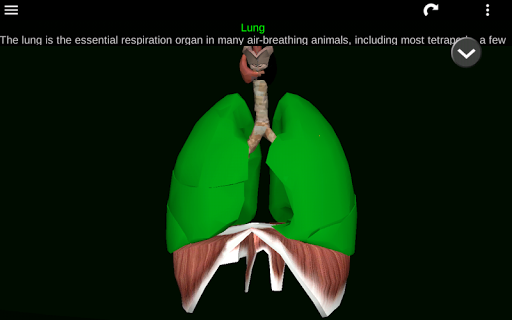

* Sistem pernafasan, yang meliputi trakea, bronkus, paru-paru dan animasi sistem ini.